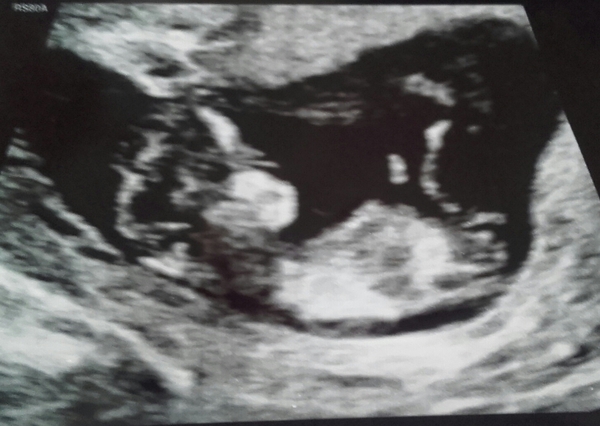

newbie87 · 28/02/2017 19:33

Not the best pic i'm afraid... how do these nub theories work?! I am desperate to find out if its a girl or boy!! x

Kskifred · 28/02/2017 20:36

Thanks Ginger! I was thinking girl too Smile

Kskifred · 28/02/2017 20:37

Ooh this is fun!

newbie and argon I would guess both boys although I'm no pro! Been reading up on in-gender.com which is quite interesting, the genitals look identical at the stage!

actually the more i look at newbie it could be girl, that's not much help is it! argon i'm still sticking with boy Grin